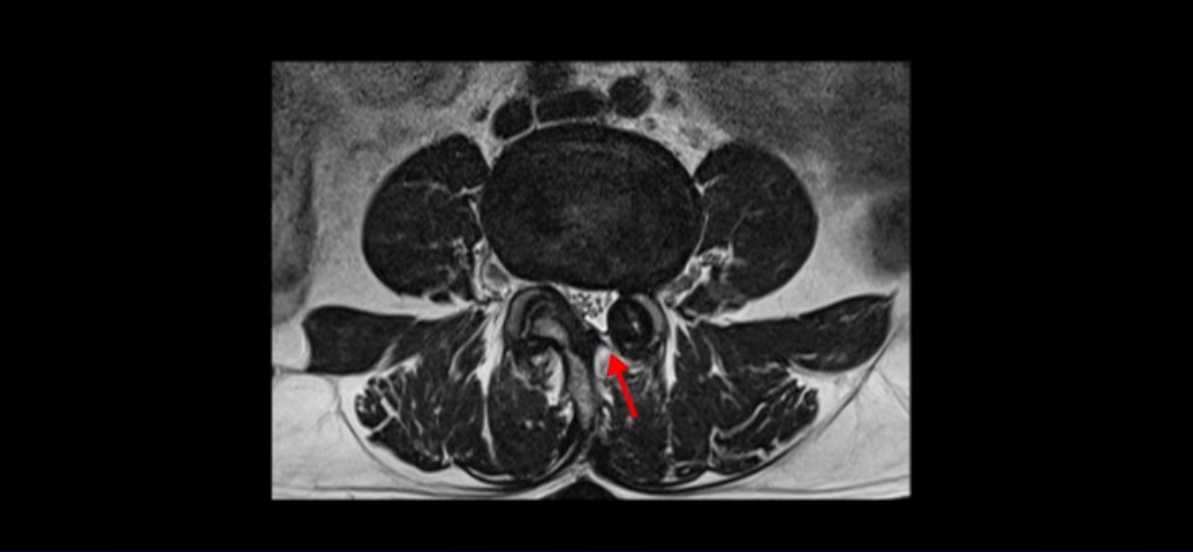

단면으로 보면 왼쪽 후궁을 제거한 흔적이 보입니다.

하지만 중심성 협착은 여전히 심한 상태입니다.

이분은 오른쪽, 왼쪽 다리에 모두 방사통이 심하고 왼쪽 다리에 마비 증상, 즉 풋드랍(족하수) 증상이 있습니다. 왼쪽 신경 가지가 빠져나가는 추간공을 보면 두 마디가 좁아져 있습니다.

이런 신경 구멍이 좁아져 있는 걸 협착이라고 합니다.